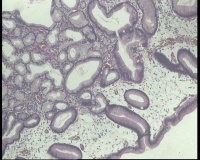

镜下见十二指肠粘液腺明显增多,排列密集,中心有少量平滑肌组织间隔,局灶腺体扩张,是十二指肠息肉还是报十二指肠腺腺瘤?

图3